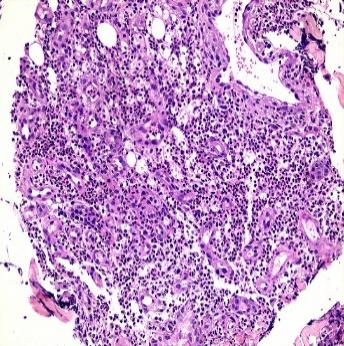

在之后的诊治中,患者病情继续好转。使用激素治疗后第3天,病损范围停止增长(图 5)。第17天,大部分创面已干燥结痂并生长出新鲜皮肤组织(图 6)。第35天,患者激素已逐渐减量至28 mg/d口服,绝大部分创面已干燥结痂,新鲜皮肤下可见青紫色血管影,原手术切口已基本愈合(图 7)。此外,病理回报送检组织除大量中性粒细胞浸润外未见异常(图 8)。患者以“手术后型PG”为诊断出院,继续口服用药并随访2周后告知创面完全愈合。

| 图 8 送检组织病理切片(15×20) |

目前,并没有针对手术后型PG的相关诊治指南。对于该病的诊断,多参考Su等[5]于2004年提出的经典溃疡型PG的诊断标准(见附表1)。该方案的主要诊断依据为临床表现与病理活检。但应特别指出的是,PG的病理表现除大量中性粒细胞浸润外并无特异度,仅为排除性诊断。